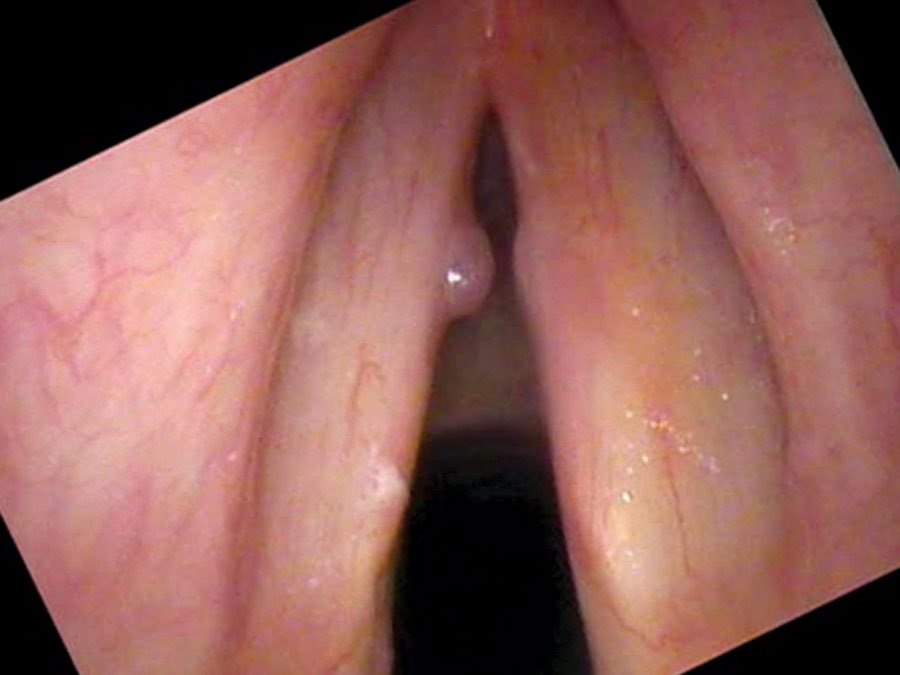

On the swelling test there is an onset delay starting at a consistent note in his mid range. I hear the roughness and the air leak in his voice when he speaks and these qualities are even more evident on swelling testing. On endoscopy there is a one-sided, spherical swelling on the vibrating edge of the left vocal cord — red in color and hemispherical. There is a smaller reactive swelling on the right side, induced by the polyp on the left striking the right cord hundreds of thousands of times in the same spot.

There is a large and slightly tortuous blood vessel crossing the surface of the vocal cord and leading to this polyp. The polyp flips up and out of the way when he speaks at a low pitch. If asked to raise his pitch, the polyp stands out and prevents him from making a higher pitch. Since he doesn’t sing, the loss of high notes bothered him less than it might have — which explains why he tolerated such a large swelling for months before seeking treatment.